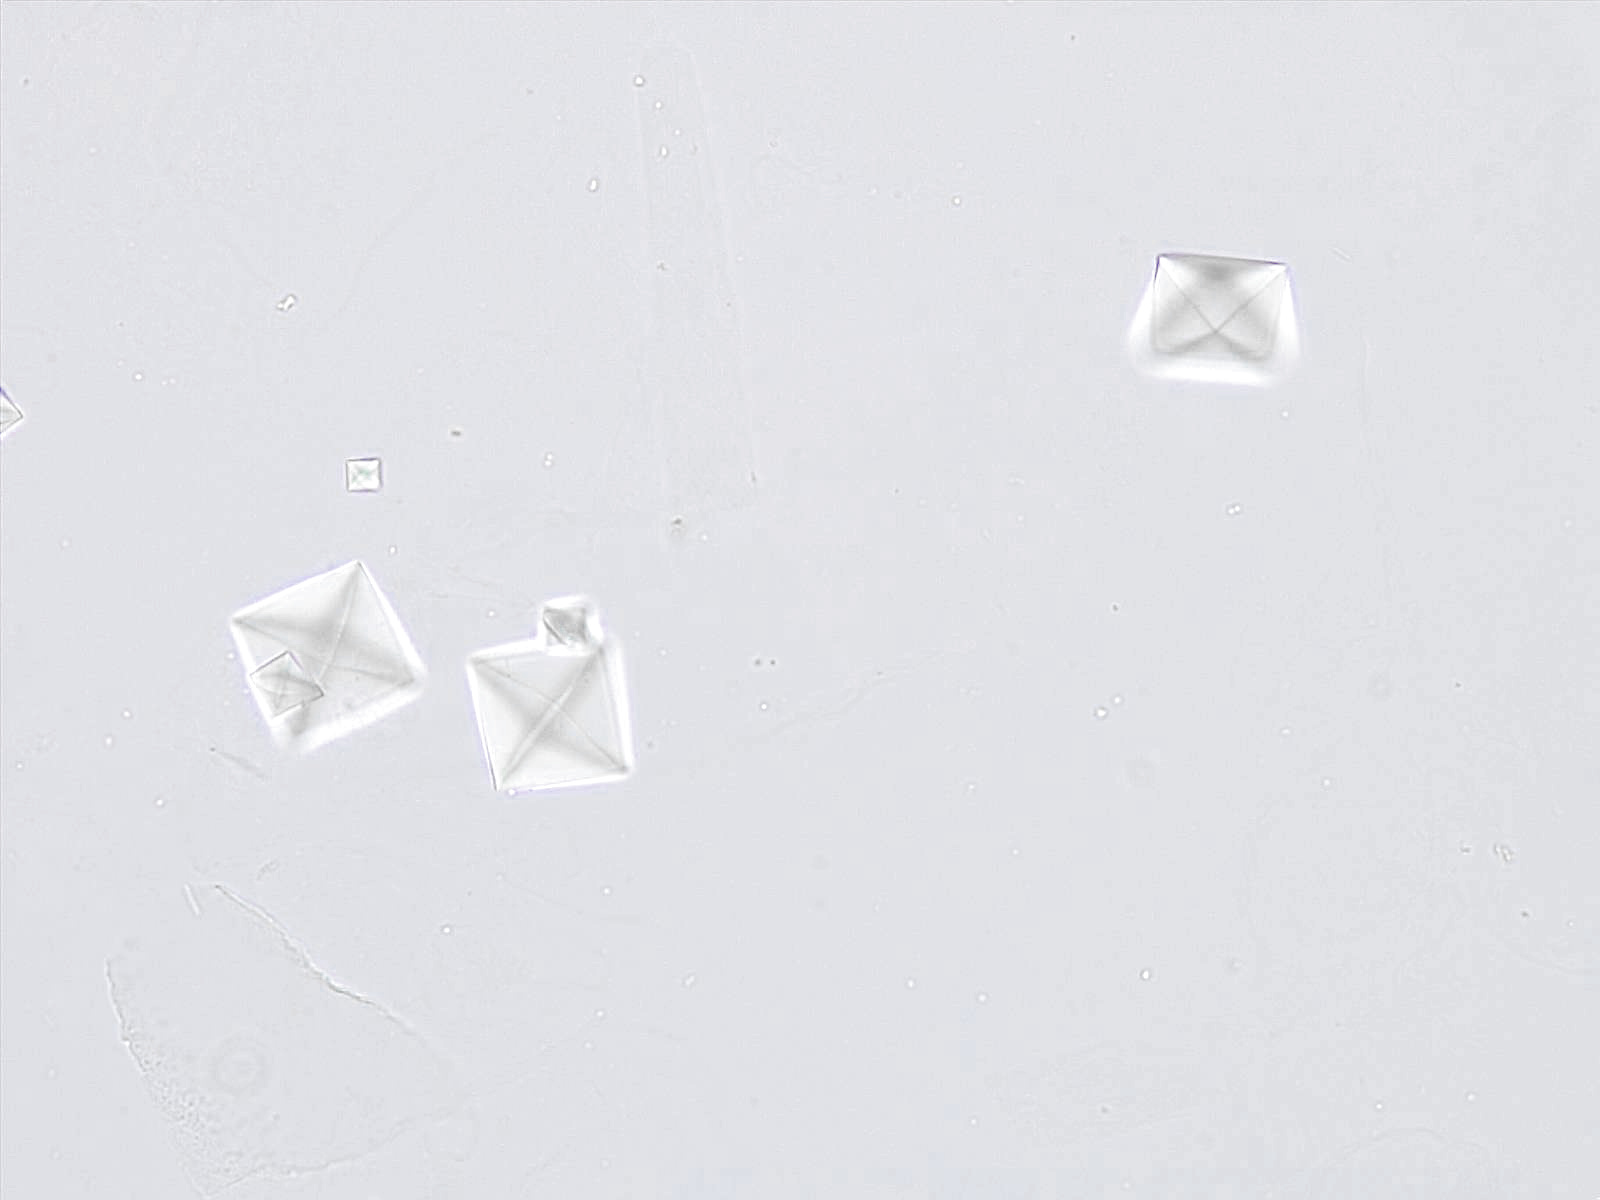

Calciumoxalaat dihydraat kristallen hebben karakteristieke bipyramidale of prismatische vormen. Onder de microscoop verschijnen ze vaak als envelop-vormige structuren, met een duidelijke en symmetrische morfologie. De grootte van de kristallen kan sterk variëren.

Doorsnede